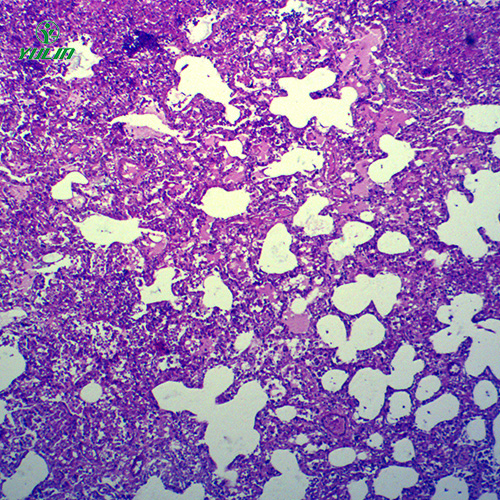

动物切片的制作需结合动物组织的特性进行优化。针对不同类型的动物组织,采用适配的处理工艺,如肌肉组织(纤维结构密集)需在切片前进行充分的软化处理,确保切片均匀;神经组织(结构脆弱)需采用更精细的切片工具,避免切片过程中出现结构破损。染色环节会根据组织特点选择染料,如观察细胞核与细胞质的关系常用苏木精 - 伊红染色法(细胞核呈蓝色,细胞质呈粉红色),观察脂肪组织常用苏丹染液(脂肪颗粒呈橘红色),通过染色清晰区分不同细胞结构与组织成分。同时,动物切片的保存需注意环境温度与湿度,避免高温、高湿环境导致切片变质或染色褪色。